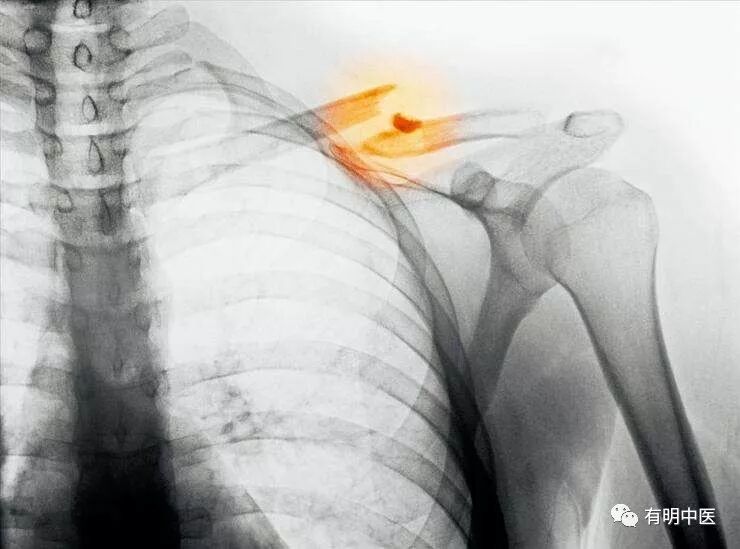

罗氏正骨法:锁骨骨折的诊断与治疗

锁骨骨折后,局部肿胀隆起疼痛,能触摸到骨折错位处的棱脊及骨擦音。患者低头含胸,健手托持伤肢及功能障碍等一系列症状。x线显示,有明显的骨折线或错位。